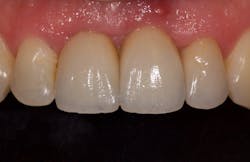

I began centering my consultation appointments on options that subsequently allowed patients to actually sell themselves on the implant treatment modality. I would present the tooth-replacement options of endo/core/crown, extraction/bridge, and extraction/implant ... and then I would explain the pros and cons of each. What I found is that patients overwhelmingly chose the root-replacement option—dental implants—over the old-school (drill-o-dontics) to reconstruct their missing tooth. Patients actually wanted an implant once they were armed with all the complete information they needed to make their decision. Having models on hand that show the difference between each option is highly effective, especially for those patients who are visual learners.

This is the paradigm shift in thinking that initiated big changes in my practice. In 2010, my little office restored 38 implant fixtures. By 2017, we were restoring closer to 200. What a difference! When patients began to realize they had treatment possibilities that may have a better long-term prognosis than the traditional replacement options, implants became a definite green light for them.

If you want to restore more implants, then you must treatment plan more implants! I believe that when dentists themselves believe in the treatment modality, it will sell itself. Ask yourself, “Is my education and training with implants good enough for me to be confident in recommending them to patients?” If not, that could be why you are not restoring as many as you would like to be. There’s an easy solution here—attend more continuing education classes or join a study club. Identify where your weaknesses exist, and get the information you need to help you provide well-informed, confident, consultations with your patients. You’ll be amazed at the number of implants you will begin to restore in your practice when the implant becomes a treatment choice instead of a last-resort selection.